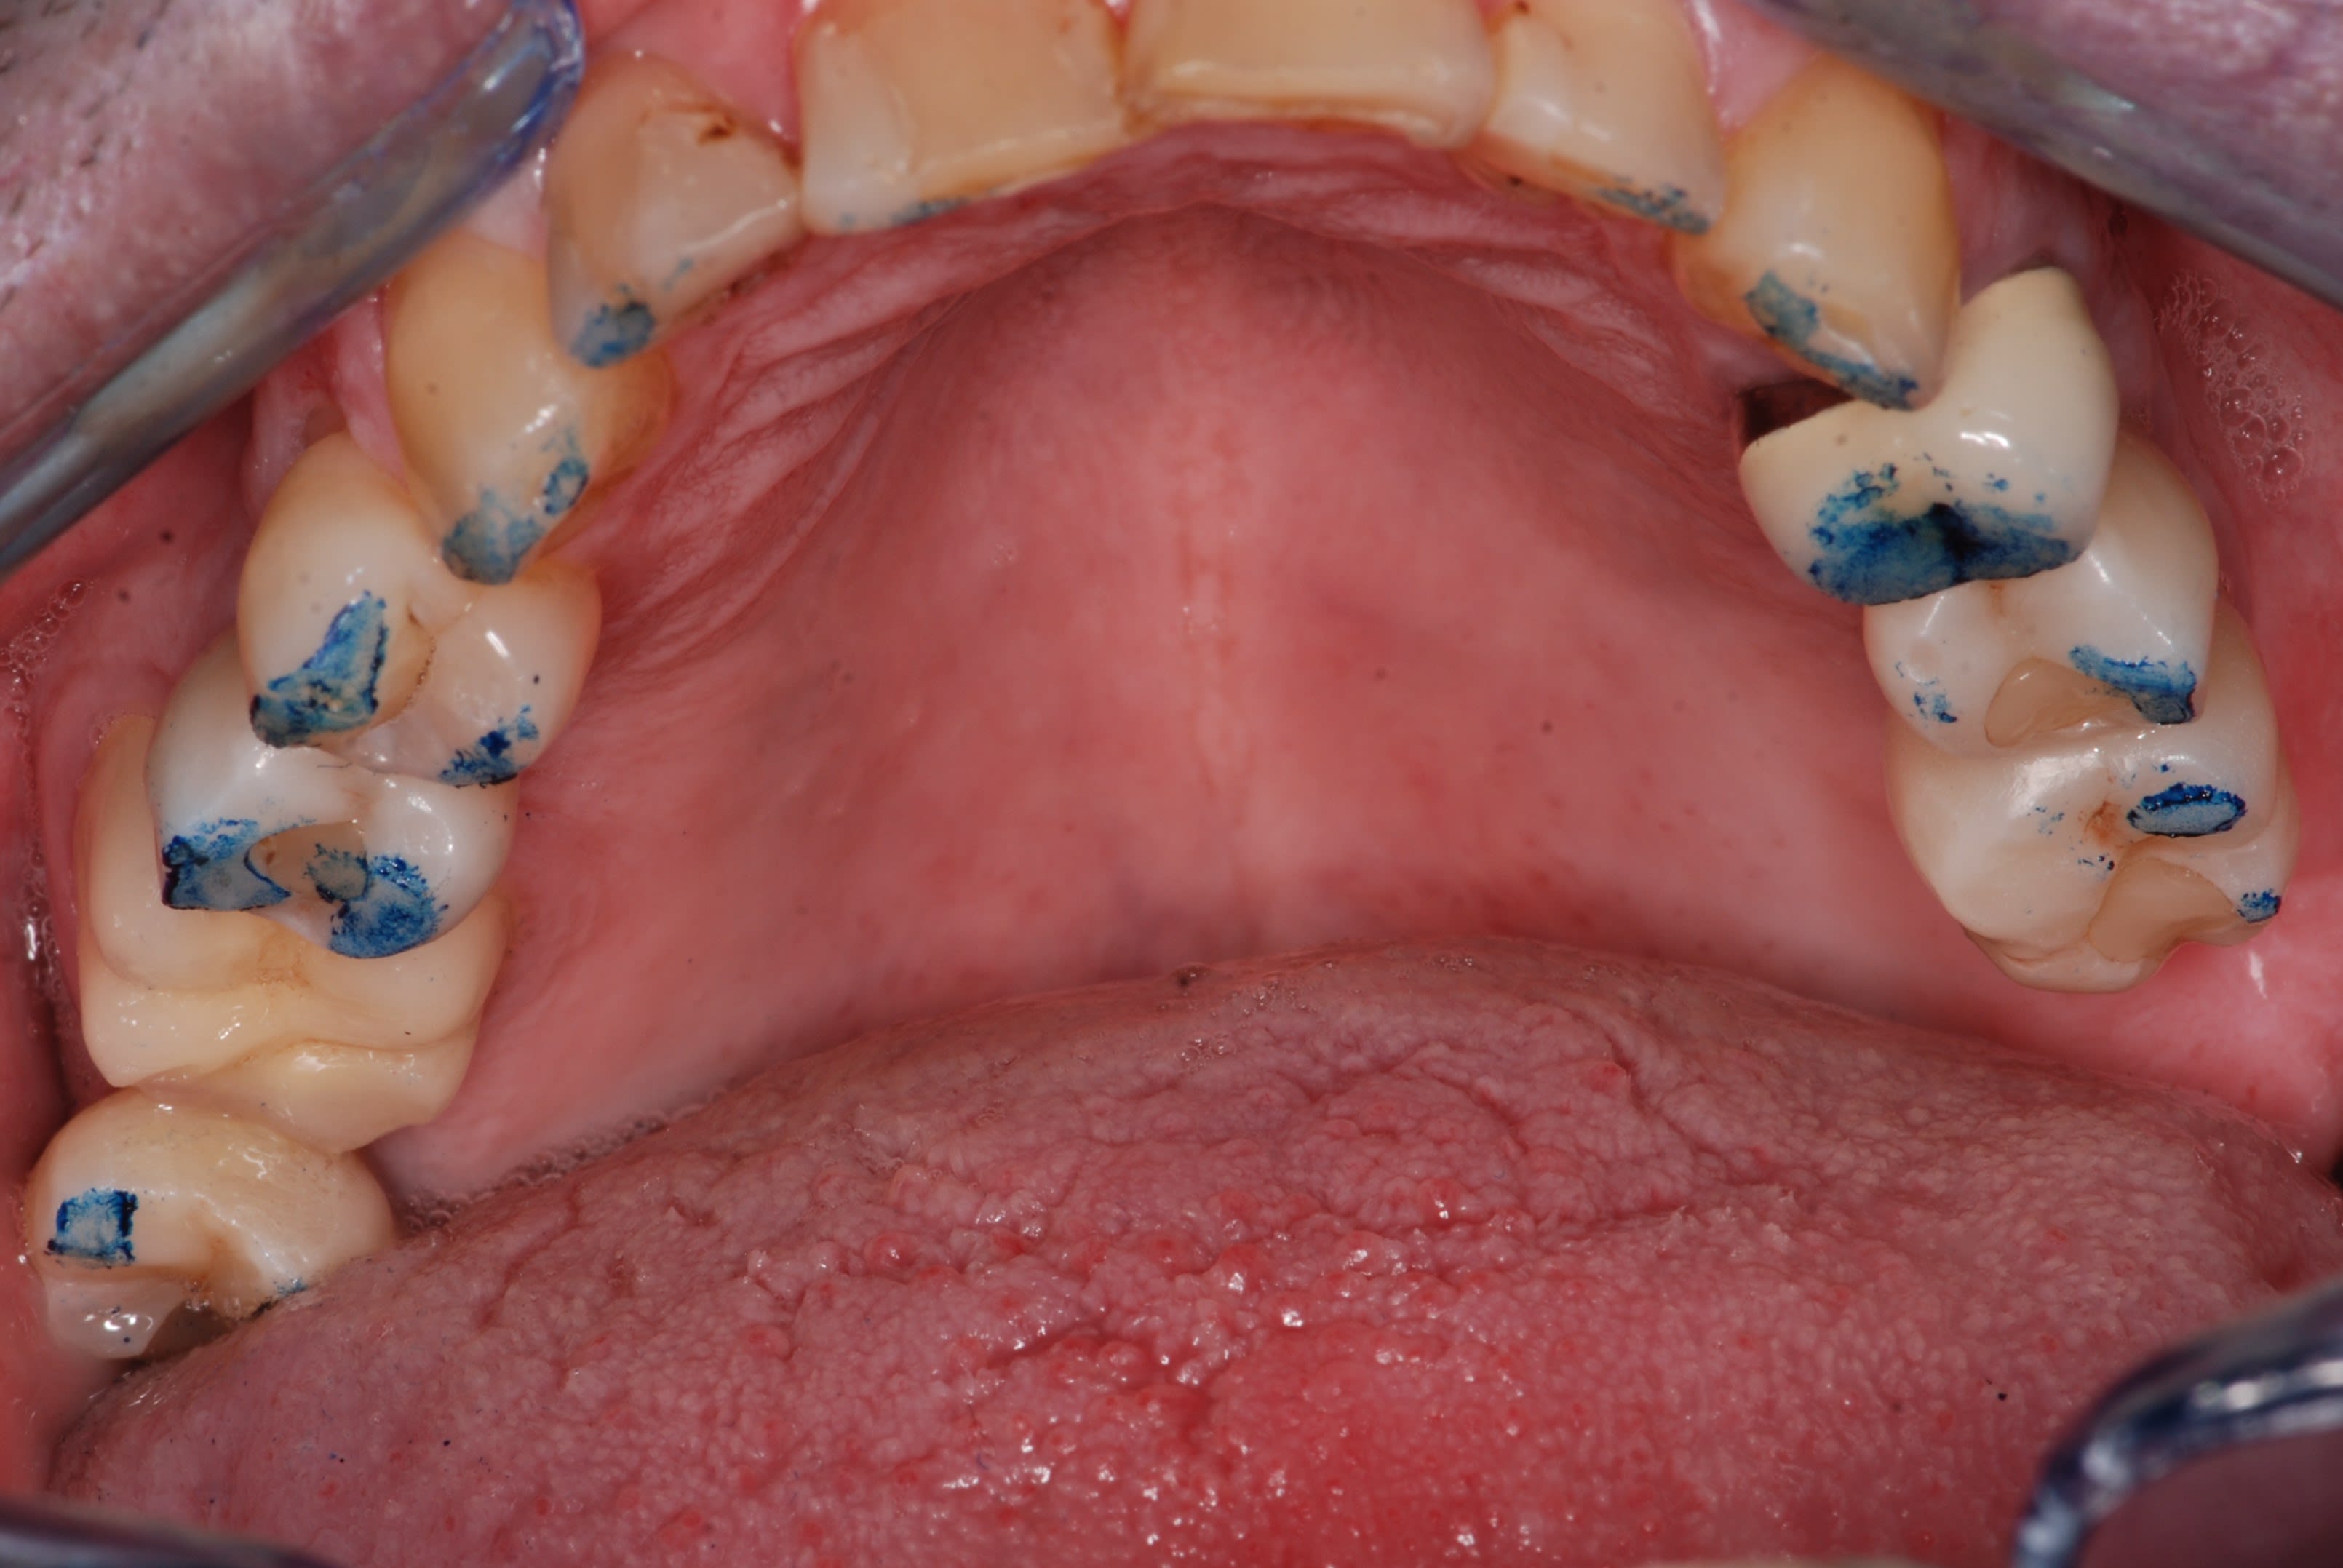

Comme promis, voici les photos du cas.

Comme je disais on dirait que la dent est remontée avec tout son parodonte...

Rien de particulier de noté au cbct fait par mon correspondant implanto. je vais lui demander les coupes